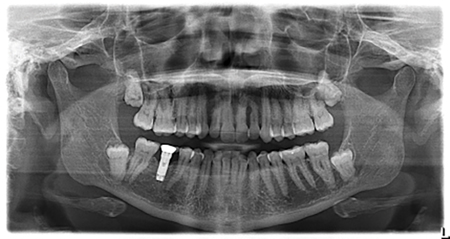

Periodontal And Prosthodontic Management Of Class III Malocclusion: A Case Report

Introduction Modern implant dentistry has been shown to yield excellent well-documented long-term results, with 10-year success and survival rates above 95%.1 Dentists now have the choice of using an array of preoperative planning tools, both conventional and computer-aided, to help them assess potential rehabilitative treatment solutions for their patients. Diagnostic wax-ups have been a critical … Read more